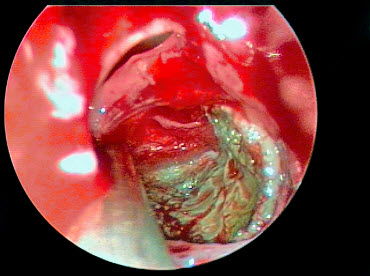

הטיפול בסינוסיטיס מתרכז במתן אנטיביוטיקה לצורך דיכוי הזיהום והקלה על תסמיני המחלה. כפי שכבר ציינו, חלק מחולי הסינוסיטיס סובלים אף מנזלת כרונית. זוהי הסיבה לכך שישנם רופאים המשלבים מתן סטרואידים לאף לטיפול מקומי בצורת תרסיס עם הטיפול הניתן לסינוסיטיס כרוני. בחלק מהמקרים ישנו צורך בהתערבות כירורגית על מנת לנקות את גתות האף מרקמה מוגלתית פגועה.

סינוסיטיס כרוני היא מחלה אלרגית

בעבר מקובל היה לחשוב שהסיבה לסינוסיטיס כרוני היא זיהום חיידקי בגתות האף ולהציע לחולים טיפול אנטיביוטי. אך המחקרים האחרונים שוללים את המקור הזיהומי של מחלה זו. למעשה, הטיפול האנטיביוטי אינו יעיל בחולים הסובלים מסינוסיטיס כרוני. הגורם האמיתי למחלה הן פטריות עובש – אלרגנים נפוצים. מחקרים מדעיים מראים שלכמות חלקיקי פטריות אלה הנמצאים באוויר ובחלל האף קשר ישיר לחומרת הדלקת ברירית גתות האף. יתר על כן, הרחקת חלקיקים אלה מהסביבה ומחלל האף גורמת להקלה משמעותית במהלך הסינוסיטיס הכרוני. נציין גם שדלקת אלרגית כרונית, שמקורה בפטריות עובש, גורמת להגדלת פוליפים באף ולעיבוי הרירית, מה שמקשה עוד יותר על הפרשת הליחה. פוליפים קיימים גורמים לזיהומים משניים ומזרזים את תהליך ההגדלה של פוליפים נוספים. כך נוצר מעגל קסמים הגורם לדלקת כרונית בגתות האף.